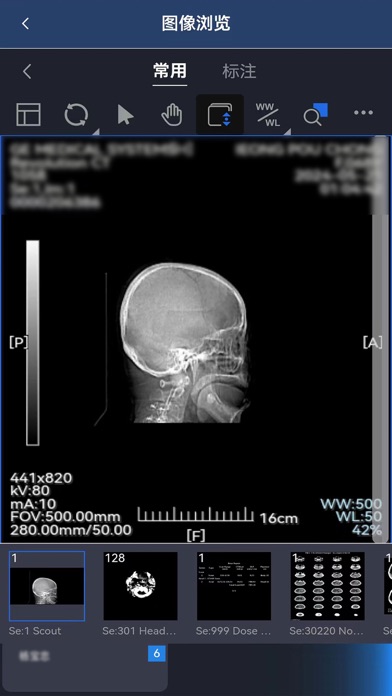

【产品说明】 东软睿影移动办公系统基于云计算和现代互联网技术,实现了各种影像数据和检查报告的云浏览,提供多种图像调整和测量功能,支持远程查看和编辑报告,使得医生可以在任意地点通过移动终端方便快捷的进行远程诊断。 【产品特性】 - 实现了包含放射、超声、内镜、病理、心电等在内的各类影像检查资料的云浏览,可随时随地浏览和诊断; - 采用身份认证机制,多种角色实现用户权限控制; - 支持多种条件查询患者检查信息,并可查看相关检查和申请单; - 多种操作模式,丰富的图像调整和测量功能; - 随时查看和编辑报告,同时支持输入模板,方便医生快速编写报告。 【联系我们】 微信公众号:东软HIT解决方案 客服电话:4006556789-7 官方网站:https://www.neusoft.com/cn1.修复多页报告无法查看的问题 2.增加token有效期自动登录